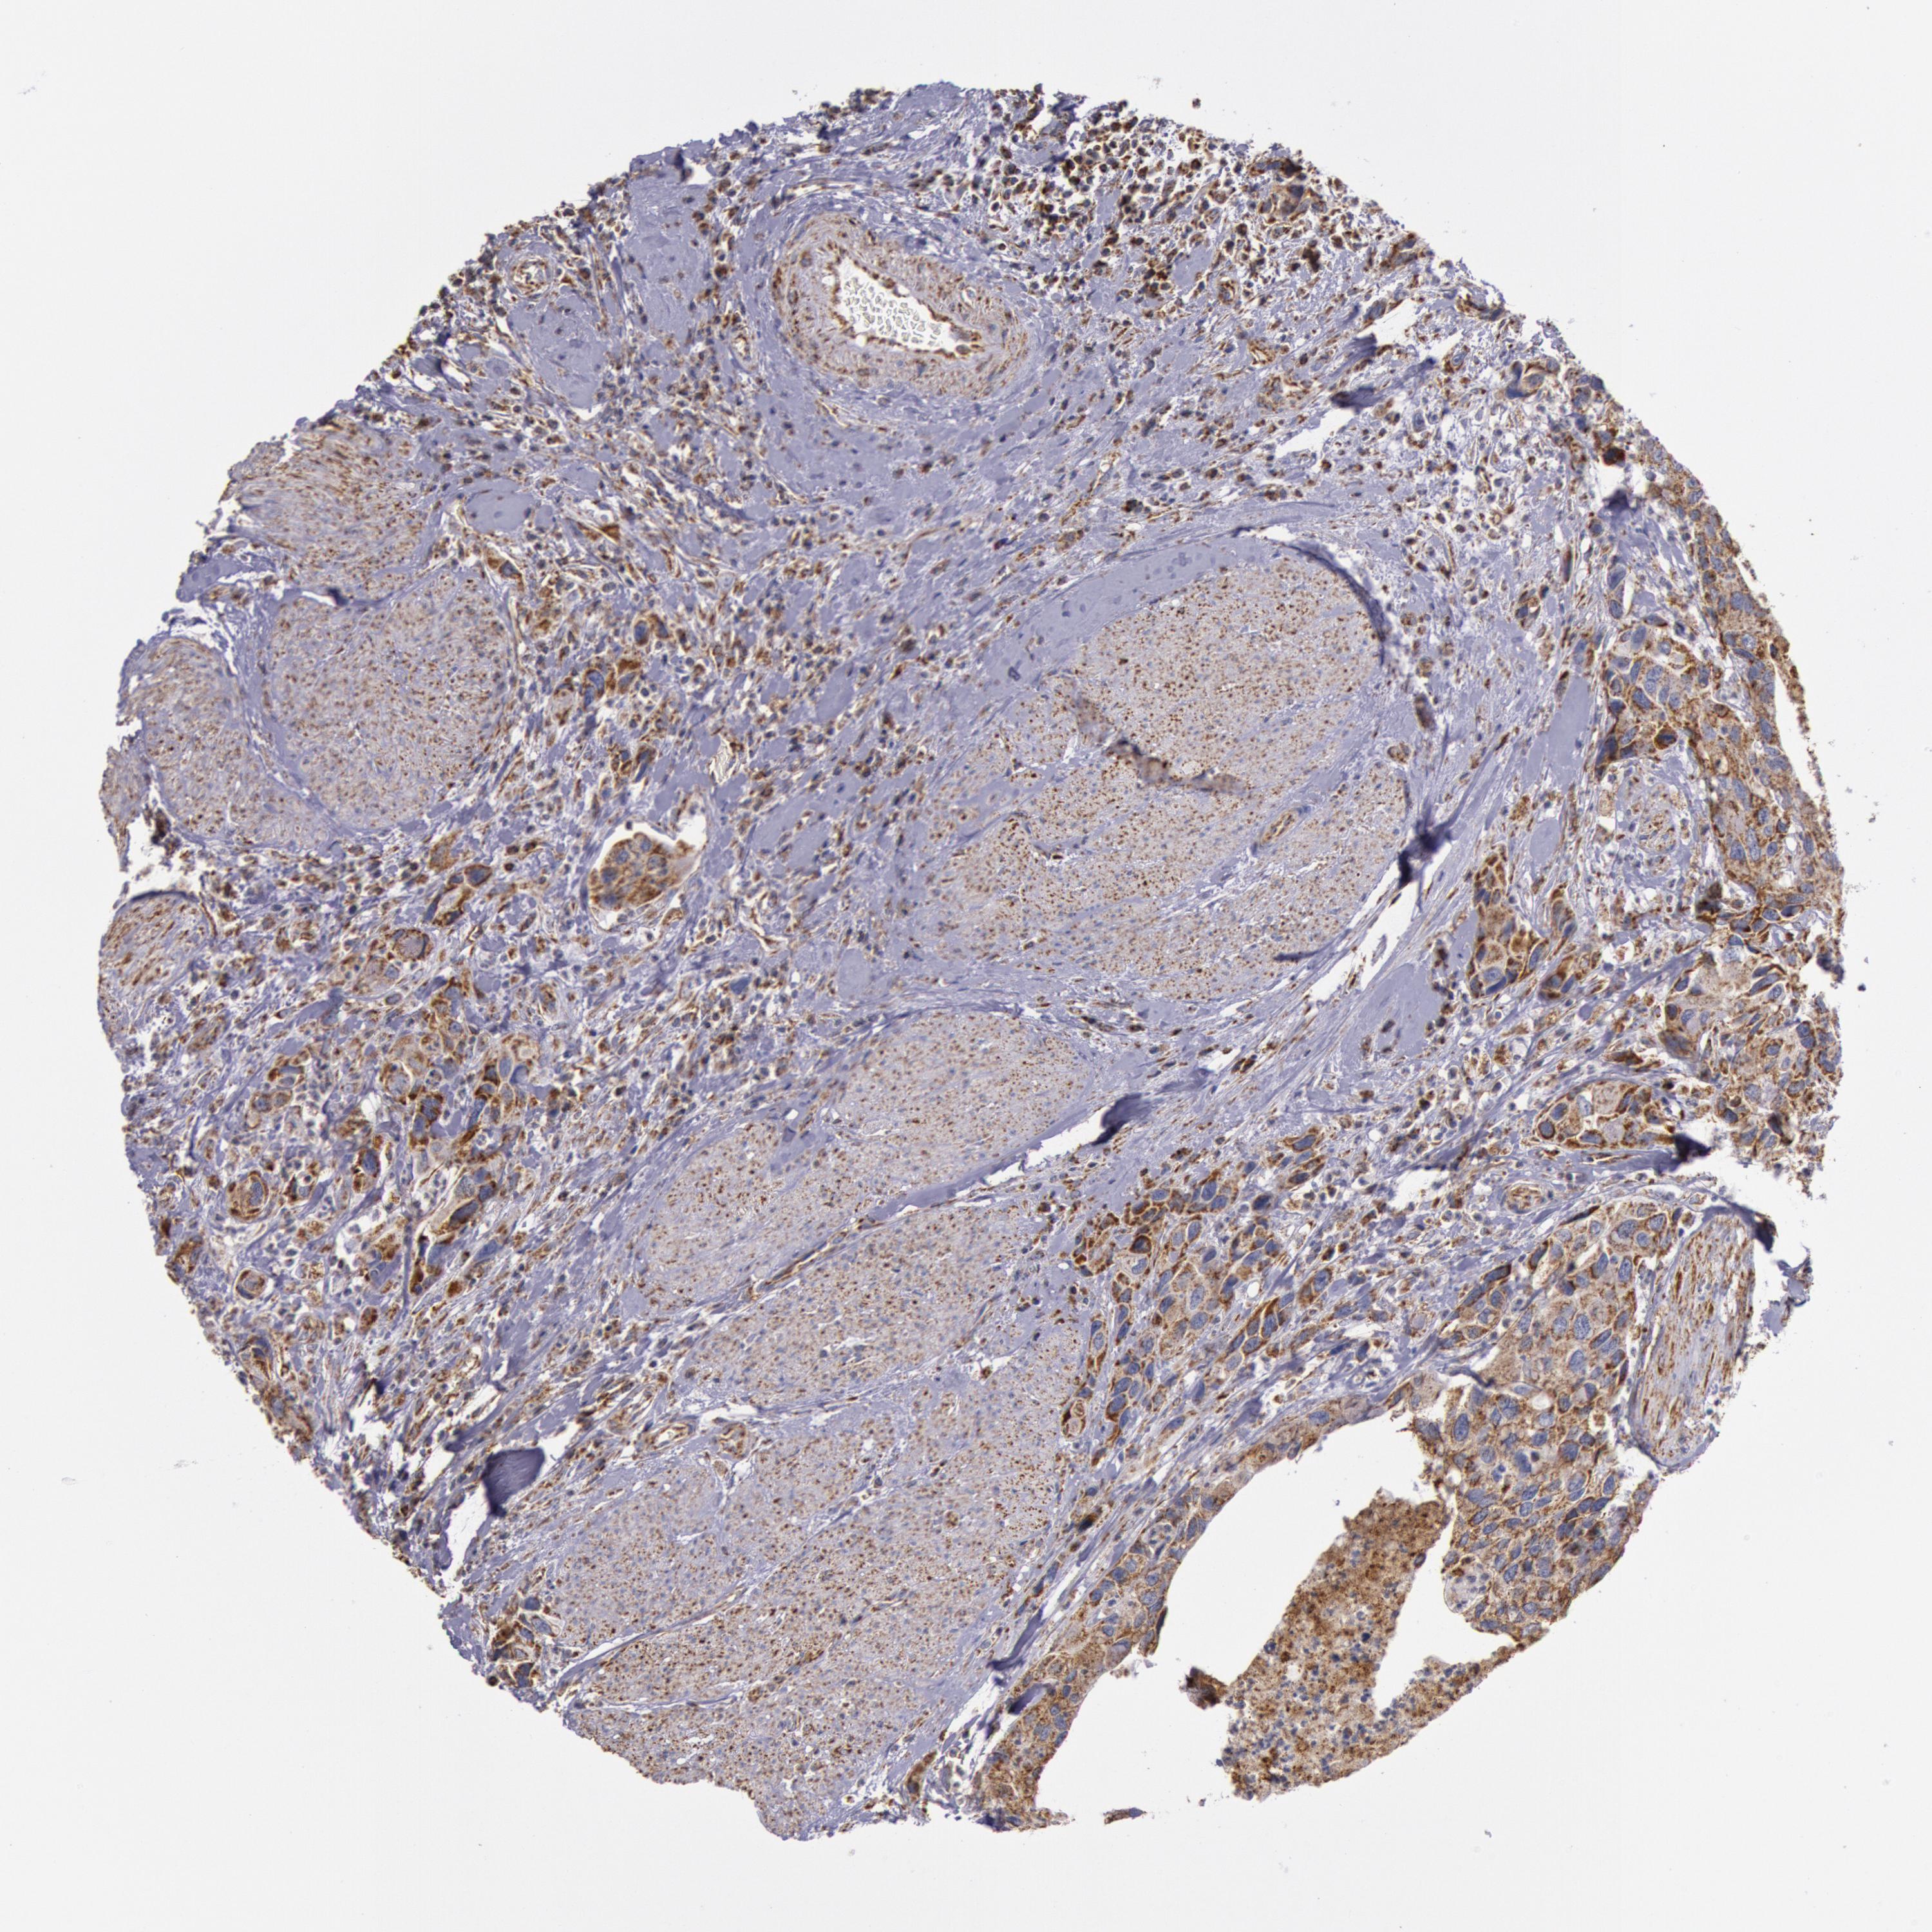

UROTHELIAL CANCER - Protein expressioni

A mouse-over function shows sample information and annotation data. Click on an image to view it in a full screen mode. Samples can be filtered based on level of antibody staining by selecting one or several of the following categories: high, medium, low and not detected. The assay and annotation is described here.

Note that samples used for immunohistochemistry by the Human Protein Atlas do not correspond to samples in the TCGA dataset.

Antibody stainingi

Antibody staining in the annotated cell types in the current human tissue is reported as not detected, low, medium, or high, based on conventional immunohistochemistry profiling in selected tissues. This score is based on the combination of the staining intensity and fraction of stained cells.

Each image is clickable and will lead to virtual microscopy that enables deeper exploration of all samples and also displays staining intensity scores, fraction scores and subcellular localization as well as patient and tissue information for each sample.

Antibody HPA001247

Staining

High

Medium

Low

Not detected

Intensity

Strong

Moderate

Weak

Negative

Quantity

>75%

75%-25%

<25%

None

Location

Nuclear

Cytoplasmic/membranous

Cytoplasmic/membranous,nuclear

Urothelial carcinoma, High grade

Urothelial carcinoma, Low grade

Adenocarcinoma, NOS